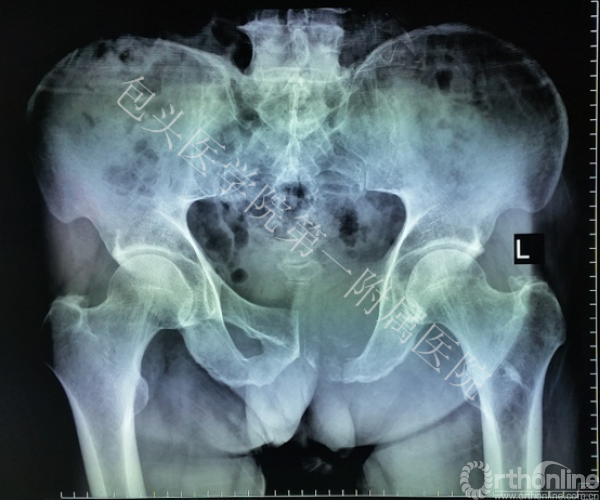

骨盆肿瘤切除后骨缺损的精细化解剖重建一直是世界性难题。传统的标准化假体仍存在诸多问题,如:无法满足不同缺损类型的重建要求,力学不稳定导致术后断裂,术后功能修复差距也很大。为此,董乐乐教授团队与西安交通大学机械制造系统工程国家重点实验室生物制造研究团队共同协作,经反复论证和数字化设计,经过3D打印为患者量身定制了个性化假体。

术前根据患者的CT数据,设计出解剖结构和肿瘤切除后与骨缺损部位完全匹配的假体,再应用“激光3D打印成形”制造出符合患者生理解剖和生物力学要求的钛合金金属假体。手术完整切除骨盆肿瘤,精确安放定制假体,达到良好的解剖和功能重建。最终,为患者提供精确化医疗和个性化医疗的服务。